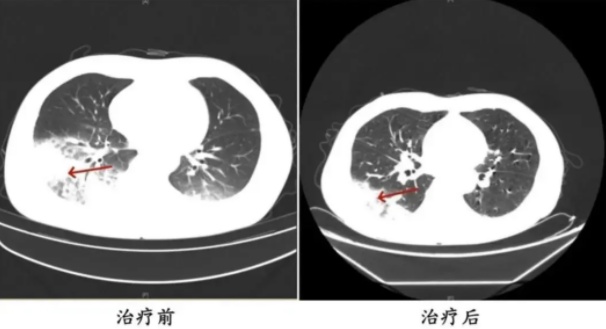

胸部CT显示李先生的左肺已出现大面积白色影像,几乎占据一半肺部。经过肺泡灌洗NGS检测,最终确认“罪魁祸首”是嗜肺军团菌。

李先生肺部治疗前与治疗后的对比